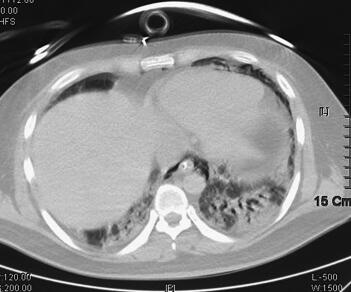

诊治经过:入科后立即予经口气管插管接呼吸机辅助通气,模式为BiPAP,参数为:FiO2 80%,Tinsp 0.95秒,PIP 30cmH2O,PEEP 15cmH2O,f 25次/分,呼吸急促,人机拮抗明显,予丙泊酚、咪达唑仑镇静,吗啡镇痛,间断维库溴铵肌松、扩容,亚胺培南-西司他汀钠1.0g静脉滴注,每8小时1次,莫西沙星400mg静脉滴注联合抗感染,乌司他丁、甲泼尼龙抑制炎症反应,氨溴索化痰,去甲肾上腺素维持血压及对症支持处理。治疗3天后患者临床症状改善不明显,高浓度给氧下氧饱和度维持在80%~85%,但患者部分炎症指标(BRT、CRP、PCT)进行性好转。考虑到患者病情危重,继续予机械通气支持,同时加大镇痛及镇静药物用量,减少患者氧耗。至4月8日血压仍需升压药维持,实验室检查NT-ProBNP 2084pg/ml,cTnI 0.35ng/ml,4月9日床边超声心动检查示心脏各个腔室大小正常,EF 45%,舒张功能减低,提示心功能不全,心肌损害。经过治疗,患者体温、BRT、CRP在入科治疗后即呈逐步下降趋势,至4月11日体温下降至正常范围,停用升压药物,血压维持120/75mmHg左右,呼吸机参数逐步下调,经皮氧饱和度维持在94%~96%左右。随后患者多次痰培养检出热带假丝酵母菌(4月7日、4月9日、4月11日、4月14日);因患者血液炎症指标逐渐下降,体温逐渐恢复正常,并无继发真菌感染的依据,考虑为定植菌可能,故未予抗真菌治疗,同时于4月12日停用亚胺培南-西司他汀钠,改用头孢哌酮-舒巴坦钠3.0g,每8小时1次,此后血常规检查血白细胞进行性升高,至4月17日白细胞计数22.72×109/L,并出现体温升高,至17日最高38.1℃,4月16日开始氧饱和度较前有所下降,波动在88%左右,尤其在吸痰后呼吸急促伴氧饱和度下降,遂予加大呼吸机支持力度,给氧浓度为60%,PEEP 14cmH2O,PSV 10cmH2O,RR 20次/分,Tinsp 1.1秒,SaO2维持在89%~94%。考虑已出现二重感染,继发肺部真菌感染可能性较大。4月17日加用氟康唑400mg每12小时1次,抗感染治疗,第2天400mg,每日1次。4月18日患者呼吸急促加剧,经加大镇静治疗及加强呼吸机支持均效果不佳,氧饱和度下降明显,只能维持在70%~80%左右;同时查血常规白细胞及CRP较前升高,两次半乳甘露聚糖试验(GM试验)回报结果阳性。临床考虑曲霉感染,予停用氟康唑,改用伏立康唑,继续加强镇静镇痛治疗,更改抗生素第2天晚上患者情况趋于稳定。之后患者体温下降,4月21日恢复至正常范围,呼吸情况逐渐改善,并能逐渐减少镇静药物剂量、下调呼吸机支持力度,同时WBC、CRP及PCT等炎症指标逐渐下降。4月25日复查胸部CT提示两肺感染较前吸收;4月25日复查超声心动图提示各个腔室大小正常,EF 65%,舒张功能减低;cTnI < 0.1ng/ml,NT-ProBNP 84pg/ml。4月26日发现胸壁皮疹,考虑为药物副反应可能,为伏立康唑的药物副反应所致,改用伊曲康唑继续抗曲霉治疗,患者皮疹逐渐消失,患者病情继续改善。至5月4日呼吸机改为CPAP模式,5月5日顺利停用呼吸机,予气管切开给氧,并停用全部鼻饲,经口进食,复查胸部CT提示双肺感染较前有所吸收,左下肺多发空洞形成,并转出ICU(图2)。5月10日,改为伏立康唑片剂序贯治疗,患者未出现皮疹以及其他不良反应,5月15日复查超声心动图提示各个腔室大小正常,EF 70%,舒张功能减低。5月20日肺功能检查提示重度限制性通气功能障碍。5月24日出院。6月8日复诊,患者自觉良好,无胸闷、气促,无发热,无咳嗽、咳痰,复查胸部CT双肺感染明显吸收、好转,左下肺空洞形成(图3)。继续服用伏立康唑片剂约2个月后停药,随访至今患者自觉良好,能够正常生活以及工作。

图3 2011年6月8日胸部CT示双肺感染较前继续明显好转,左下肺空洞形成